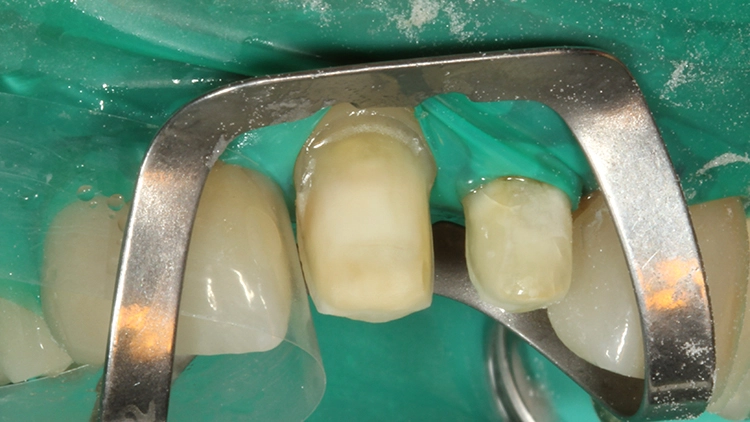

Im Einsetztermin erfolgte nach Abnahme der Provisorien, der Reinigung der präparierten Zähne und der Einprobe der Arbeit nach ästhetischer Zustimmung durch die Patientin die Vorbehandlung der Teilkronen bzw. Veneers mit Schneidekantenfassung. Die Vorbehandlung der Zirkonoxid-Klebeflächen erfolgte bereits laborseitig mit 50 ?m Aluminiumoxid [18].

In der Abbildung 15 ist die Teilkrone für den Zahn 11 mit dem fast vollständig evaporierten Primer zu sehen. Zeigt sich ein derartiges Evaporationsbild vorzeitig, muss Material nachappliziert werden. Die Verklebung von Veneers und Teilkronen unter Kofferdammisolierung ist sicherlich sinnvoll.

Ebenso sinnvoll ist es, Teilkronen einzeln zu verkleben und nach Versäuberung des Befestigungskomposits die als nächstes zu verklebende Teilkrone nochmals einzuprobieren. Verständlicherweise erfolgt dann erst die Vorbehandlung dieser Teilkrone. (Auch jetzt kann trotz Kofferdamm immer nochmal eine Klebeflächenkontamination passieren.)